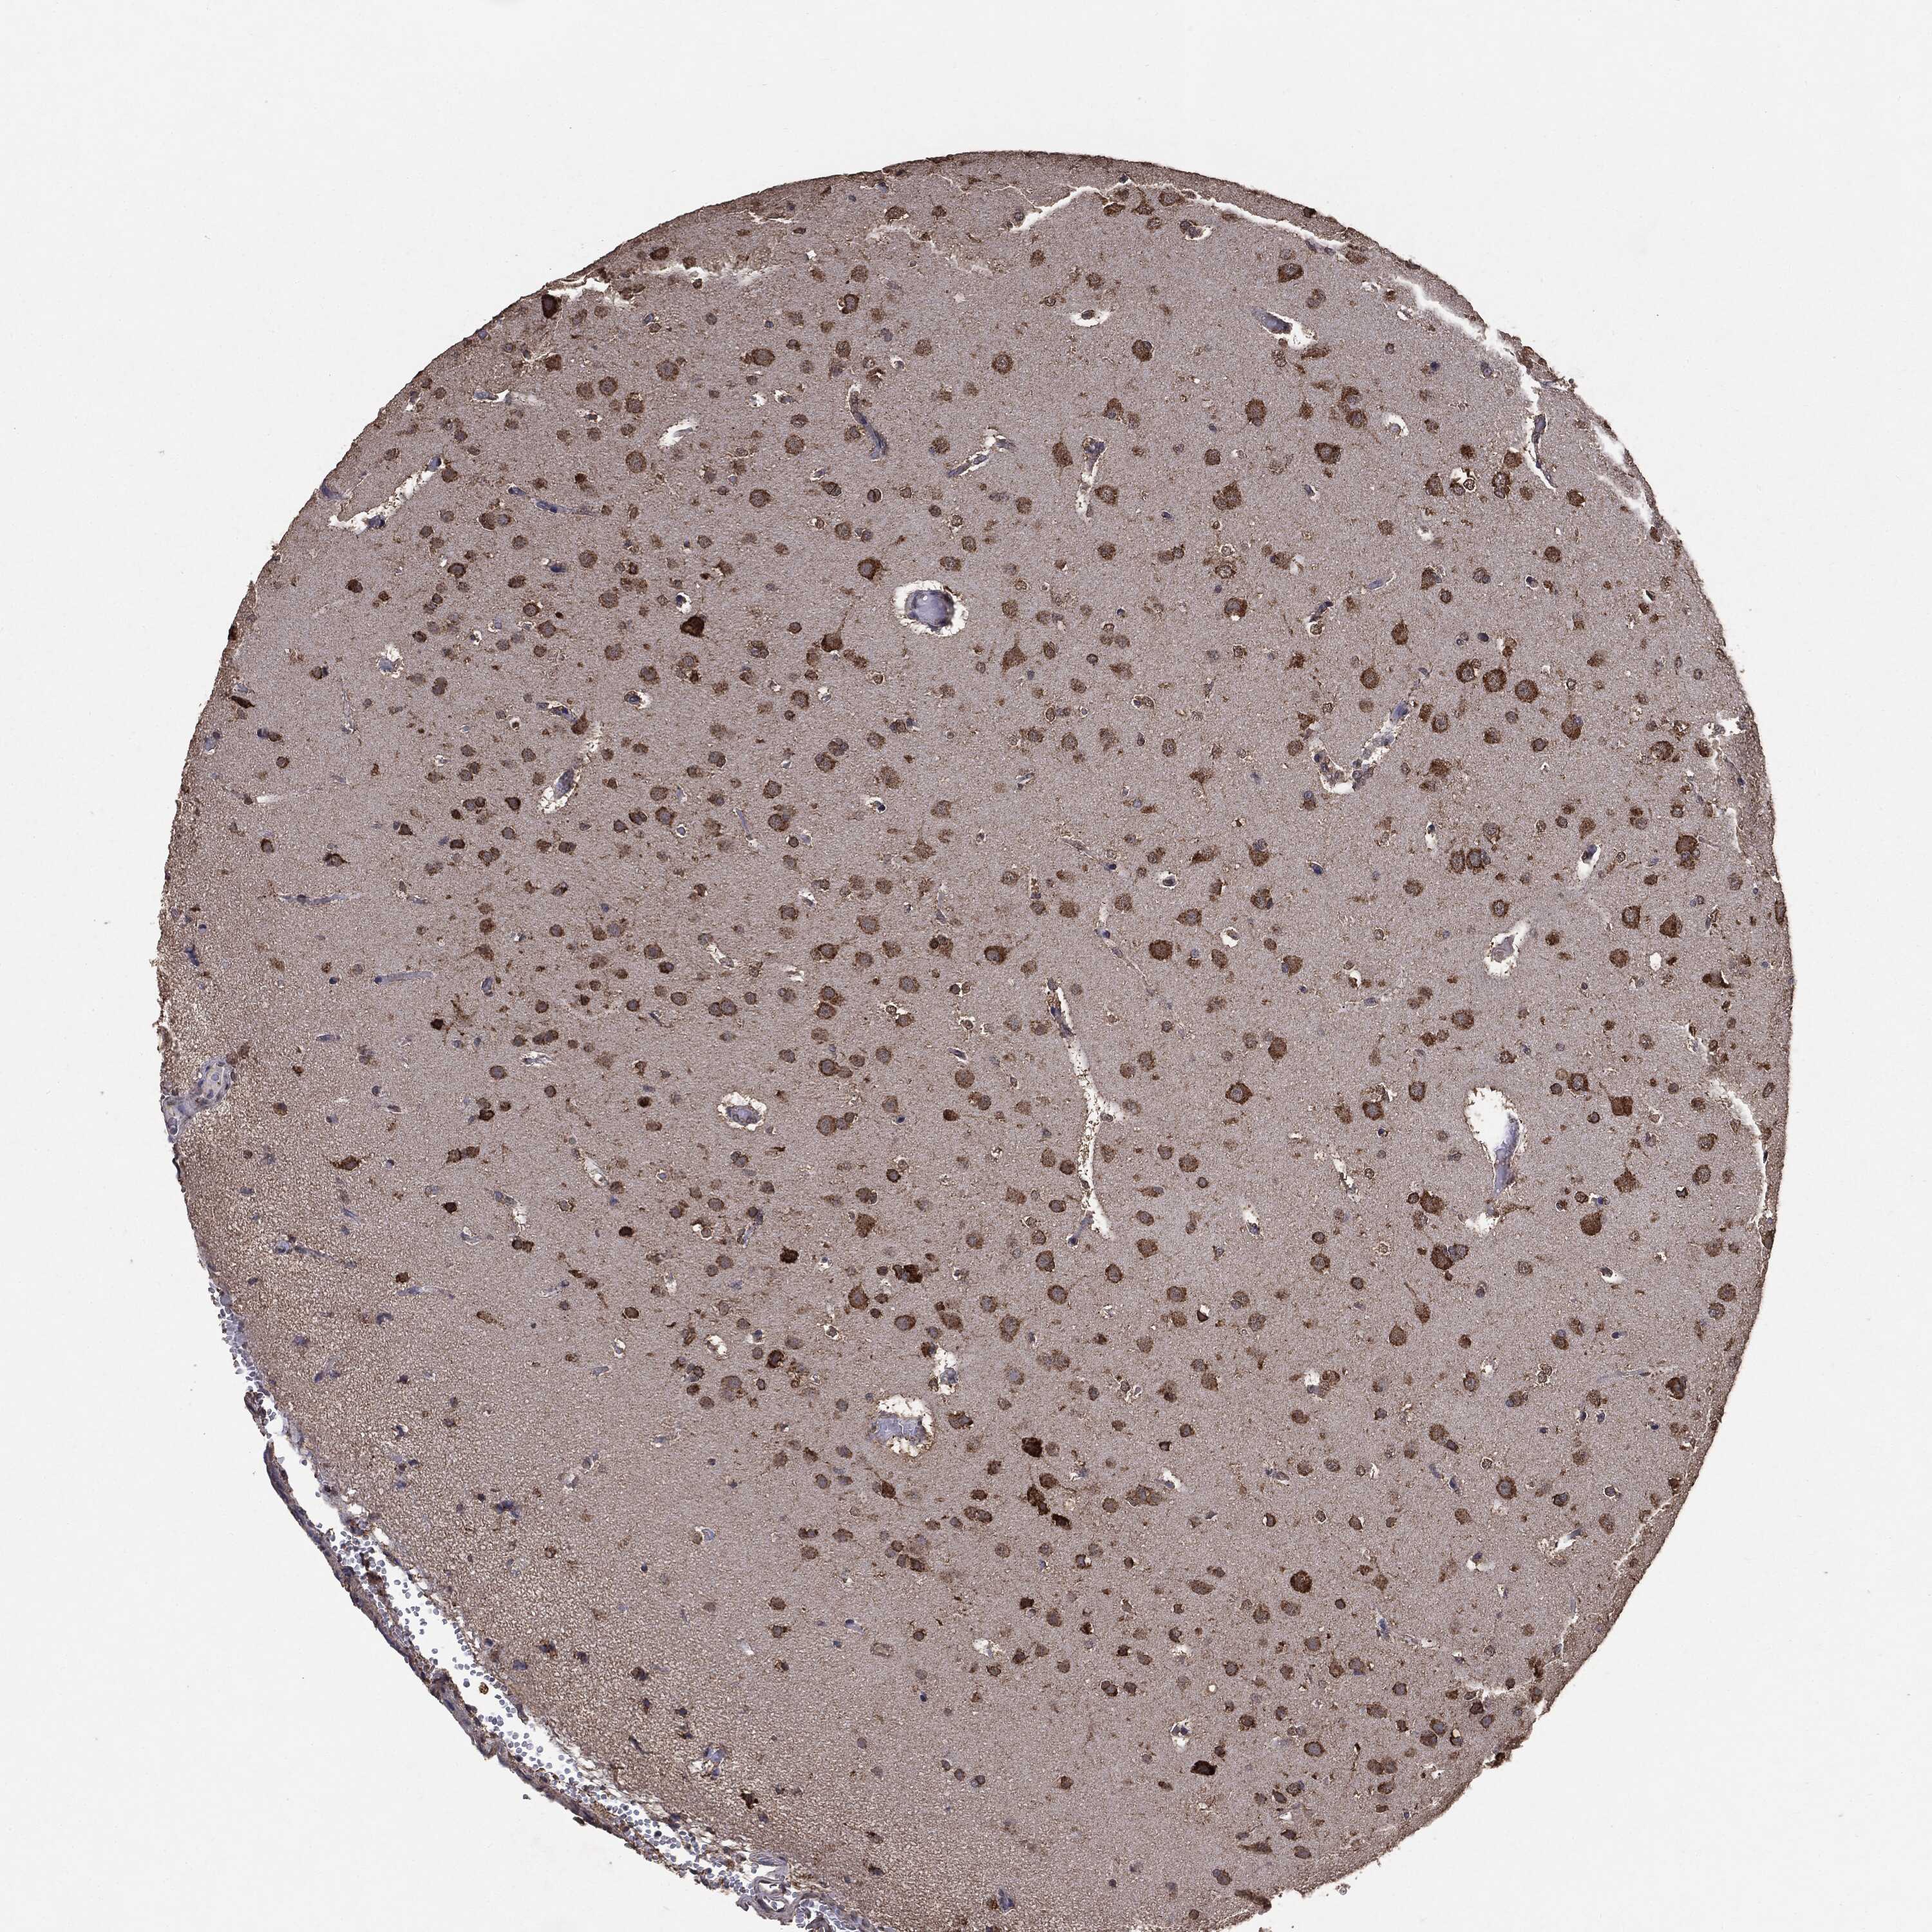

GLIOMA - Protein expressioni

A mouse-over function shows sample information and annotation data. Click on an image to view it in a full screen mode. Samples can be filtered based on level of antibody staining by selecting one or several of the following categories: high, medium, low and not detected. The assay and annotation is described here.

Note that samples used for immunohistochemistry by the Human Protein Atlas do not correspond to samples in the TCGA dataset.

Antibody stainingi

Antibody staining in the annotated cell types in the current human tissue is reported as not detected, low, medium, or high, based on conventional immunohistochemistry profiling in selected tissues. This score is based on the combination of the staining intensity and fraction of stained cells.

Each image is clickable and will lead to virtual microscopy that enables deeper exploration of all samples and also displays staining intensity scores, fraction scores and subcellular localization as well as patient and tissue information for each sample.

CAB069425

CAB080053

CAB080065

CAB080070

CAB080081

CAB080095

CAB080097

Staining

High

Medium

Low

Not detected

Intensity

Strong

Moderate

Weak

Negative

Quantity

>75%

75%-25%

<25%

None

Location

Nuclear

Cytoplasmic/membranous

Cytoplasmic/membranous,nuclear

Glioma, malignant, Low grade

Glioma, malignant, High grade

Glioma, malignant, NOS